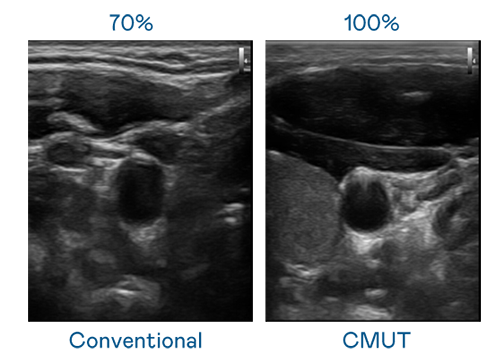

CMUT 技术是一种用电容式微机电元件来产生超音波讯号的技术。与传统 PZT 压电式技术相比,CMUT 频宽增加 30%,更宽频的超音波讯号让影像解析度大幅提升,是实现高影像品质医疗超音波扫描、促进精准医疗发展的关键技术。

大频宽带来超清晰影像

超音波影像的解析度高低,首先取决于探头能发出的讯号频宽。来利国际w66 CMUT 可提供高清晰的超音波讯号,提供高频宽、高灵敏度、影像纹理细节更高的超音波影像,协助医护人员缩短影像判读时间及利用精准的医疗影像进行诊断。